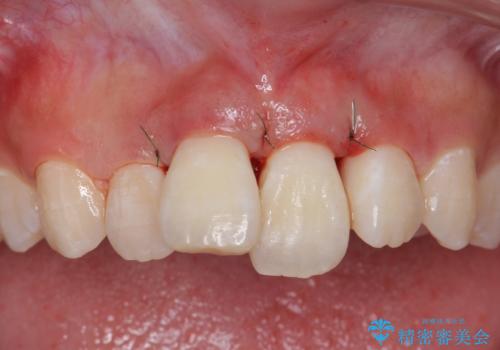

前歯の角度や歯ぐきのラインに差が大きかったため、やむなく神経をとり、歯ぐきの手術を行い出来るだけ歯ぐきのラインを整えるようにしました。

手術をしなければ左上1番の歯ぐきのラインは左上2番よりも下にきてしまい、長さの短い歯になってしまうところでした。

治療結果には大変満足されていました。

- 31万円(ジルコニアクラウン(スタンダード)10万円x2、仮歯 1万円x2 ファイバーコア 2万円x2 ジンジペクトミー 5万円)費用は治療当時の料金となります

笑っても大きく歯ぐきが見える方ではなかったので、歯ぐきのラインが目立つことはなかったです。

手術をしなければ左上1番の歯頚ラインは左上2番よりも短い位置になっていたため、歯自体の長さが不自然なほど短くなってしまったと思います。